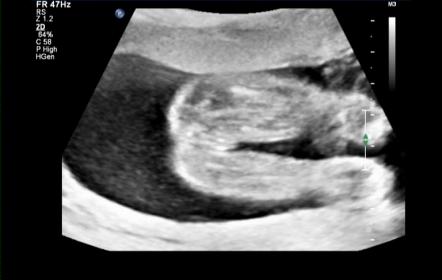

Hello lovely ladies :) Soooooo had my 20 week anatomy scan this morning and as you all guessed it right bubs is a :ballerina: We're over the moon that she is healthy!! The tech took a nub shot to confirm gender though which I thought was a little odd as Im so used to seeing potty shots so Ive snapped a few off my dvd and included her nub shot but just hoping to get your confirmation too please xx